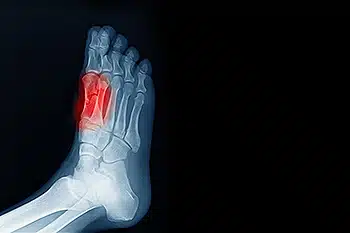

Sesamoiditis is a condition that involves inflammation of the small sesamoid bones located beneath the big toe joint. These bones help absorb pressure and assist in movement, but excessive strain can lead to irritation and pain. Common causes of sesamoiditis include repetitive stress from activities like running, dancing, and jumping, as well as wearing high heels or improper footwear. Individuals with high arches or an abnormal foot structure may also be more prone to developing this condition. Symptoms often include pain beneath the big toe, swelling, and difficulty bending or moving the toe. The discomfort may worsen with activity and improve with rest. If you have pain in this part of your foot, it is suggested that you consult a podiatrist who can accurately diagnose and treat sesamoiditis.

Sesamoiditis is a condition of the foot that affects the ball of the foot. It is more common in younger people than it is in older people. It can also occur with people who have begun a new exercise program, since their bodies are adjusting to the new physical regimen. Pain may also be caused by the inflammation of tendons surrounding the bones. It is important to seek treatment in its early stages because if you ignore the pain, this condition can lead to more serious problems such as severe irritation and bone fractures.